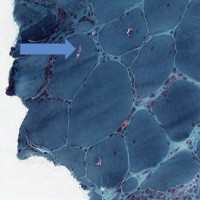

- Muscle biopsy shows perifascicular inflammation and atrophy with sparing of the central fascicle.